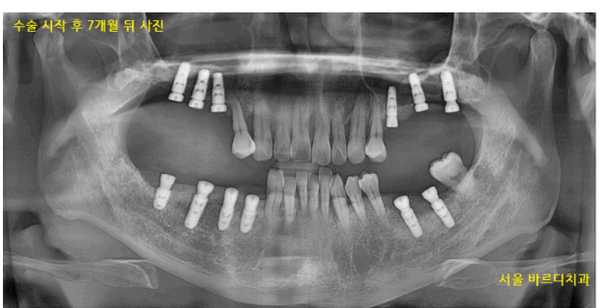

230827

윗니 어금니 부분입니다.

잇몸 뼈가 치아 뿌리를 거의 잡지 못하고있습니다.

남아 있는 잇몸뼈는 3.4mm

바로 위에는 상악동이 버티고 있습니다.

임플란트는 최소 8mm정도 길이를 심으니까

뽑고 나서 뼈이식으로 만들어줘야하는 잇몸뼈의 길이가 5mm가 넘네요.

231218

임플란트 뼈이식 흡연을 하시기 때문에

충분히 기다렸습니다.

5월달에 왼쪽 위부터 수술했는데

7개월정도 지나 보철을 올려드렸어요.